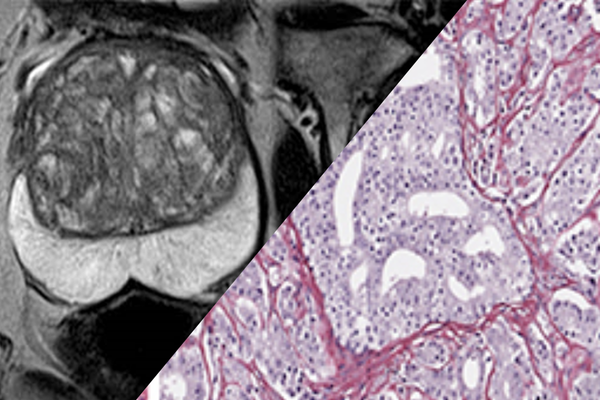

Radiomics and phatomics for prostate cancer

We are working towards developing radiomics and phatomics models to estimate the presence or absence of aggressive prostate cancer in all sub-regions of the prostate, using a combination of manually chosen texture and shape features, as well as features from trained deep learning models using the above framework.

What do we do? signal and image processing, machine learning, deep learning

Collaborations with: Kresk (Portugal)

Interested in knowing more about this topic? Contact people: Raquel Conceição, Seán Finn, Daniela Godinho

Accepting internships and Masters!

Imaging Biomarkers using Advanced Diffusion MRI Sequences

Advanced diffusion MRI sequences provide unique in vivo insights into tissue microstructure. Based on these advanced sequences, we are developing and validating a paradigm-shifting diffusion MRI framework capable of distinguishing key pathological features in tumors and ischemic stroke lesions. This technique integrates state-of-the-art sequence design, advanced data modelling, Monte Carlo simulations, and histological validation.

What do we do? MRI sequence programming, processing and modelling diffusion MRI data with application in stroke and tumors, validation through Monte-Carlo Simulations and histological data

Collaborations with: Champalimaud Foundation (Portugal), Instituto Superior Tecnico (Portugal), University of Trento (Italy).

Interested in knowing more about this topic? Contact people: Rafael Neto Henriques

Accepting internships, Masters and PhDs!